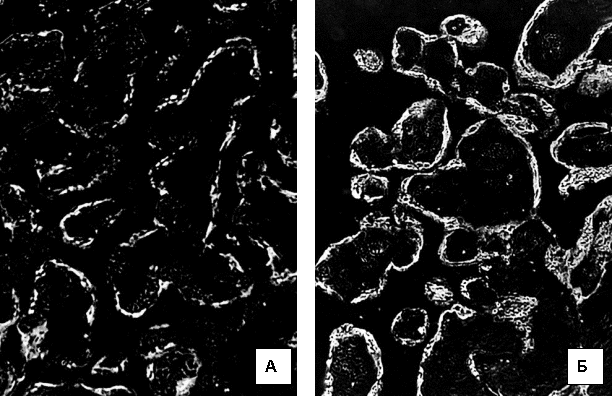

Рис.1. Світіння

цитоплазми трофобласта хоріальних ворсинок після обробки люмінолом при довжині

хвилі 425 нм. А) контрольна група. 39 тижнів вагітності. Б) залізодефіцитна

анемія. 39 тижнів вагітності. Мікроскоп ЛЮМАМ-8. Об.20х. Ок.10х.

При строкових

пологах (37-40 тижнів гестації) інтенсивність світіння цитоплазми трофобласта

хоріальних ворсин після обробки люмінолом було вищим, ніж у попередні терміни

вагітності. У групі контролю середня інтенсивність світіння була оцінено у

184,1±4,27. Однак, це світіння набувало рис вираженого фракціонування по площі

цитоплазми (3а). При ЗДАВ світіння було оцінено в 204±5,71, а фракціонування по

площі цитоплазми, такого, як у групі контролю не відмічалося. Різниця між

групами дослідження за критерієм Mann-Whitney була вірогідною (p<0,001).